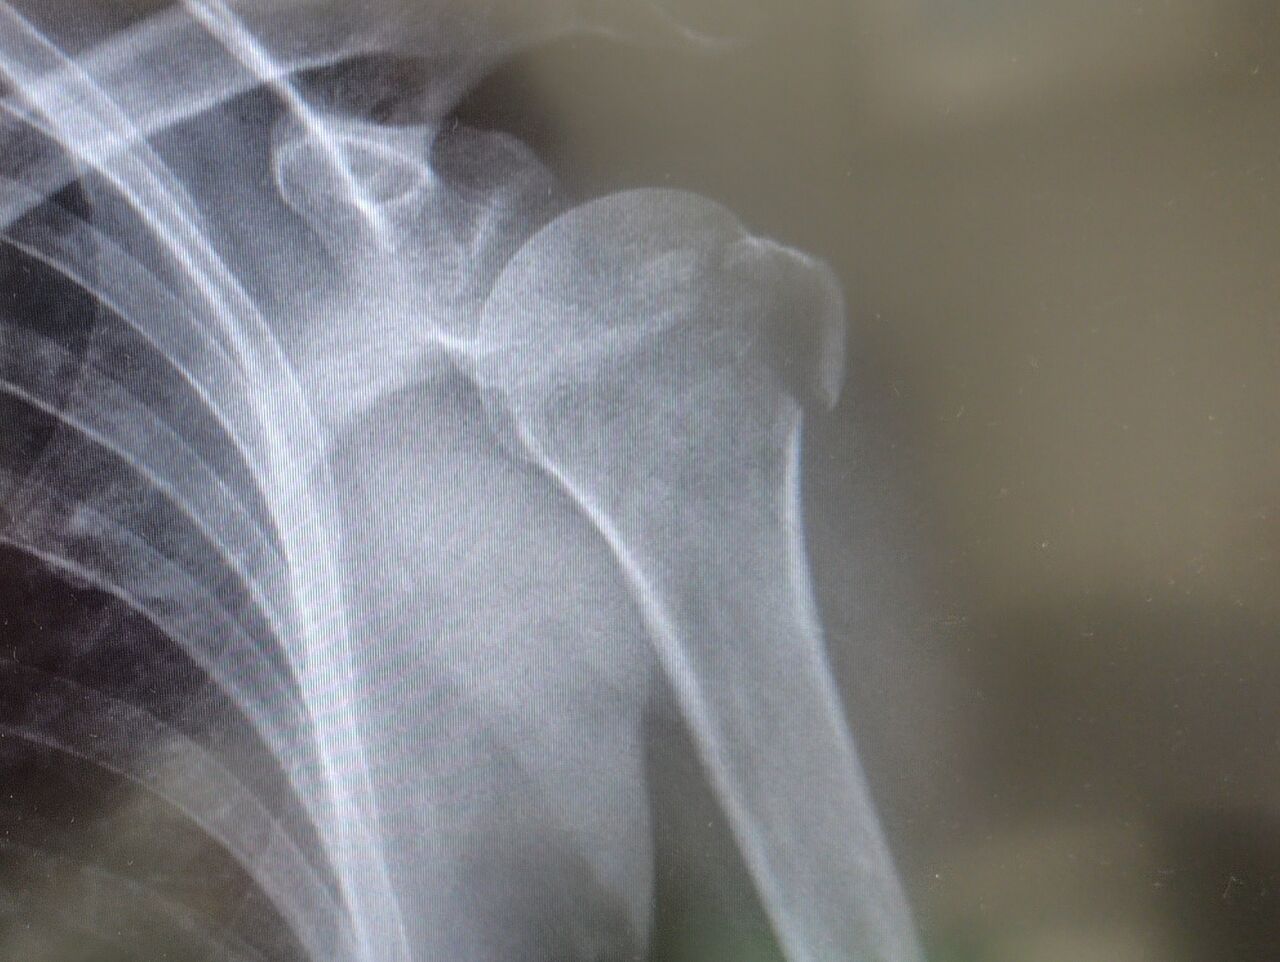

「ん〜〜、レントゲン撮ってみたほうがいいね」

と言われ、レントゲン撮影したとろ、、

折れてるぅー!?😨

翌日、外科で診察してもらったところ、上腕骨骨折だって…😭

しかも上腕骨にヒビも入ってました…